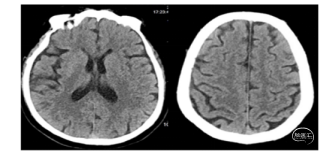

术前CT:转入我院后急行CT检查,未见明显出血,左侧大脑后动脉条索状高密度影(图1),因患者自发病在6小时内。

手术过程:局麻,右美托咪定镇静,5F造影导管行造影检查,结果提示:左侧椎动脉相对优势,V1段连续复合弯;左侧大脑后动脉P1段中段开始远端未见显影(下图2)。

将6F 088 Neuron MAX长鞘输送至左侧椎动脉V2段中段, Powler微导管、Transend微导丝(300cm)行“首过效应”判断可见:原闭塞部位缓慢前向血流后撤出微导管,同轴交换跟进4 MAX抽吸导管(下图1)。

一次性抽吸取栓成功开通左侧大脑后动脉,造影显示左侧大脑后动脉全程显影良好,流速正常,P2段局部稍狭窄,无明显造影剂外溢(图2、3 )。

结束手术,体外见一黄白色长条状栓子(图4),股动脉穿刺至大脑后动脉再通。

术后患者镇静状态,NIHSS评分未评。

术后镇静、镇痛、控制血压,术后动态复查头颅CT见左侧枕叶、丘脑、中脑片状梗死区,无明显出血。术后予以拜阿司匹林(100mg)、硫酸氢氯吡格雷(75mg)、阿托伐他汀(60mg)。患者于术后第1天清醒,神经功能逐渐改善。